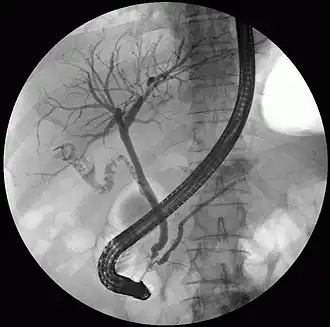

The pancreatic duct or duct of Wirsung (also, the major pancreatic duct due to the existence of an accessory pancreatic duct) is a duct joining the pancreas to the common bile duct. This supplies it with pancreatic juice from the exocrine pancreas, which aids in digestion.

The pancreatic duct joins the common bile duct just prior to the ampulla of Vater, after which both ducts perforate the medial side of the second portion of the duodenum at the major duodenal papilla. There are many anatomical variants reported, but these are quite rare.[2]

1. Bile ducts:

2. Intrahepatic bile ducts

3. Left and right hepatic ducts

4. Common hepatic duct

5. Cystic duct

6. Common bile duct

7. Ampulla of Vater

8. Major duodenal papilla

15. Pancreas:

16. Accessory pancreatic duct

The front border of the liver has been lifted up (brown arrow).[1]